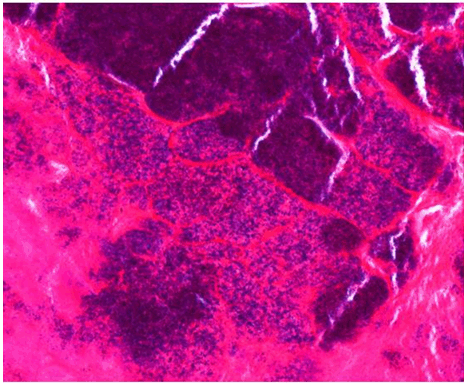

A 47-year-old male was transferred to our hospital due to fever and severe fatigue. Although he had been experiencing symptoms for several months and visited doctors near his home several times, his condition was not diagnosed and he took antimicrobial drugs for a few days. On admission, he exhibited a systolic murmur and moderate mitral regurgitation with large vegetation on echocardiographic findings (Figure 1). Streptococcus mitis was detected in his blood culture and he was diagnosed with infective endocarditis. He also exhibited Janeway lesion, petechial hemorrhage on his conjunctiva and Roth spots on his fundus (Figure 2). His clinical presentation is typical. Computed tomography scan and magnetic resonance imaging scan revealed small multiple embolization to the brain, spleen, and kidney. Cardiac surgery was too risky because he also had severe coagulopathy and his mitral regurgitation was not so severe as needed the surgery. Although intensive medical treatment was administered, his severe infection was not controlled, and it led to multi-organ failure. On day-15 of hospitalization, the patient succumbed to multi-organ failure. Autopsy revealed huge vegetation (30×15×5 mm) in the two-thirds around the mitral valve (Figure 3). Histological analysis demonstrated that the vegetation was composed of necrotic tissue and neutrophils, along with numerous Gram-positive cocci (Figure 4) that destroyed the tissue of the mitral valve and the wall of the left atrium (Figure 5). An autopsy also revealed embolization of kidney and spleen and necrotic intestines, which had caused multi-organ failure.

Figure 4: Histological examination demonstrated that the vegetation was composed of necrotic tissue and neutrophils, with numerous gram-positive cocci.